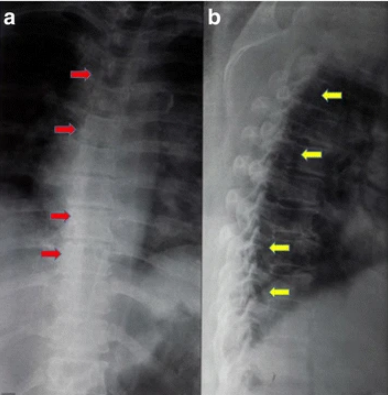

進(jìn)行了胸部X光檢查,結(jié)果正常(見圖1)。T1加強(qiáng)磁共振成像顯示,Th8和Th9椎體后方硬膜內(nèi)位置有一個規(guī)律性的低強(qiáng)度病變,主要位于左側(cè)。該病變壓迫了脊髓向左。在T2加強(qiáng)磁共振成像中,病變相對于正常脊髓具有等強(qiáng)度(圖2)。

1 胸腔區(qū)域、前后側(cè)和側(cè)面的普通X光片。a 前后視角顯示脊柱畸形及胸椎周圍的腫塊沉積過程(紅色箭頭)。b 側(cè)面圖顯示脊柱管某一水平處有退行性腫瘤沉積(黃色箭頭))